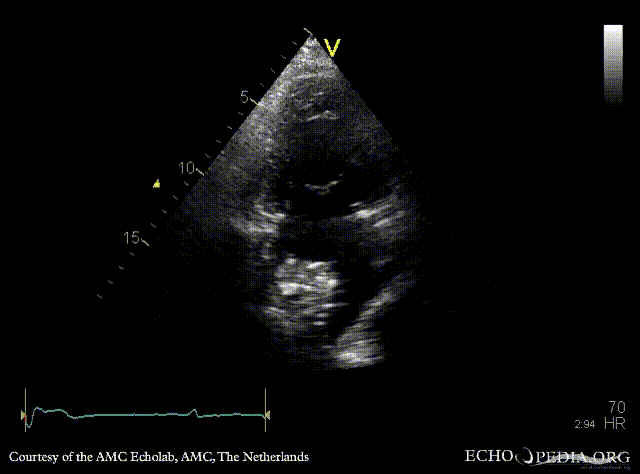

| Courtesy of: AMC Echolab, AMC, The Netherlands | |

| A4CH | A2CH |